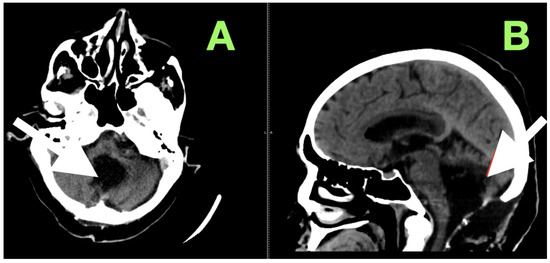

Fourth Ventricle Epidermoid Cyst: Case Report of Precision Telovelar Microsurgery, Functional Preservation, and Lifelong Surveillance

Background and Clinical Significance: Fourth ventricular epidermoid cysts are among the least frequently encountered intracranial tumors (less than 1%). Their slow growth pattern along cisternal and subarachnoid spaces, and their close proximity to neurovascular structures (brainstem–cerebellar), create difficulty for surgical treatment. Total [...] Read more.

Background and Clinical Significance: Fourth ventricular epidermoid cysts are among the least frequently encountered intracranial tumors (less than 1%). Their slow growth pattern along cisternal and subarachnoid spaces, and their close proximity to neurovascular structures (brainstem–cerebellar), create difficulty for surgical treatment. Total removal is often complicated by the capsule’s adherence to eloquent structures and requires a thoughtful surgical approach of weighing radical resection versus neurologic/function preservation. This case description provides an example of using careful clinical–radiological correlation and anatomy-dissecting microsurgery as a method of permanent decompression and neurologic recovery with low operative risk. Case Presentation: A 57-year-old female presented with impaired stability of gait, gaze-evoked nystagmus, appendicular ataxia, minimal ipsilateral hypotonia, and mild bulbar dyscoordination. Imaging (MRI, MRA) revealed a large, lobulated mass that was lobulated and avascular centered in the left cerebellar hemisphere, with an extension into the vermis and cisterna magna, and partial filling of the fourth ventricle with classic epidermoid imaging. Resection was performed via a midline suboccipital telovelar approach with microsurgery, relying on native arachnoid planes and quadrant opportunities of decompression, while preserving critical neurovascular structures. A thin rim of capsule intimately adherent to the floor of the ventricle was intentionally left to minimize irreversible cranial nerve injury. Histology showed keratinizing stratified squamous epithelium with laminated keratin and cholesterol clefts. Following resection, truncal stability, limb coordination, and ocular pursuit improved without additional deficits. Initial and 3-month postoperative MRI showed total decompression, re-established CSF pathways, and no recurrence. Conclusions: This case demonstrates that maximal safe resection (with function preservation) through natural anatomy corridors can achieve excellent neurologic results in fourth ventricular epidermoids. Lifelong MRI surveillance will be needed due to the srisk of delayed recurrence even after near-total resection. Full article

Show Figures

Figure 1